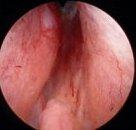

Die Operation der gutartigen Prostatavergrößerung ist bei Komplikationen oder fehlender Besserung unter medikamentöser Therapie notwendig. Zum Einsatz kommen die Hobelung der Prostata (TURP), die Schnittoperation (Adenomektomie) oder schonende Prostata-Laserverfahren. weiterlesen...

- Transurethrale Resektion der Prostata (TURP): Indikationen und Technik

- Prostata Greenlight Laserung (KTP-Laser)